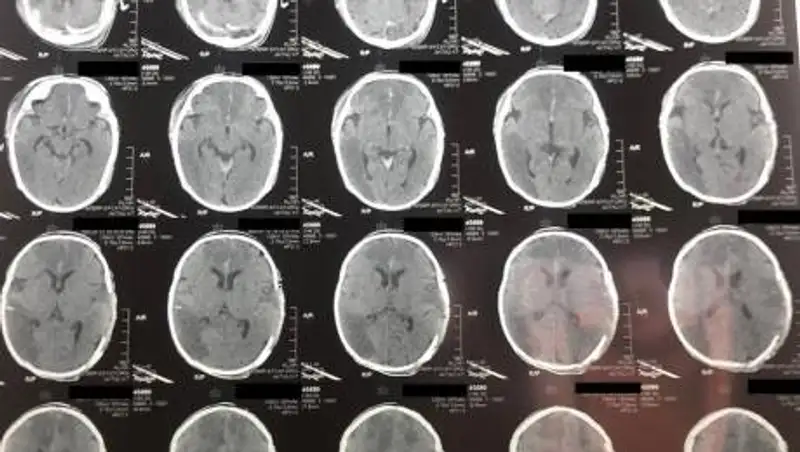

По информации lada.kz, 9 января ребенка с диагнозом "Острое нарушение мозгового кровообращения" (инсульт новорожденных) доставили в Мангистаускую областную многопрофильную детскую больницу.

У двухмесячного младенца зафиксировали отек головного мозга, дислокационный синдром и кому I-II степени.

10 января состояние ребенка удалось стабилизировать. В экстренном порядке ему провели операцию по трепанации черепа, которая продлилась два часа.